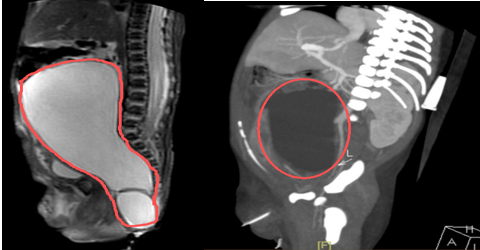

萌萌出生后即刻被转入新生儿科,曾纪晓主任迅速组织了新生儿科、影像诊断科等专家团队对这位小生命进行细致的评估。腹盆腔肿瘤巨大,考虑“畸胎瘤III型”,导致子宫、膀胱受压前移,与结直肠关系密切,腹主动脉及双侧髂动脉受压移位同时位于骶尾部,容易产生皮肤压疮导致肿瘤破溃,靠近肛门口极易继发感染。

腹部MR+增强CT均提示腹盆腔巨大肿瘤。